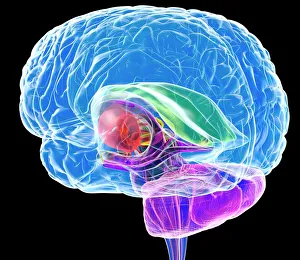

The central nervous system, the intricate network that governs our every thought and movement, is a marvel of complexity. From the delicate cerebellum tissue to the detailed light micrograph capturing its essence, we are reminded of its importance in maintaining balance and coordination. Anatomy comes alive as we explore the human brain from an inferior view. The intricacy of brain fibers is revealed through DTI MRI scans like C017/7099 and C017/7035, showcasing their vital role in transmitting information throughout this extraordinary organ. Artistic renderings bring us closer to understanding the medulla oblongata's significance within the brain. Its portrayal in various artworks allows us to appreciate how it controls essential functions such as breathing and heart rate. As we delve deeper into studying the central nervous system, models of the human brain provide invaluable insights into its structure and organization. Lateral views reveal countless regions responsible for cognition, emotion regulation, sensory perception, and motor control. Microscope slides offer glimpses into nerve cells' intricate architecture—a testament to their ability to transmit electrical signals at lightning speed. Meanwhile, glial stem cell cultures captured under a light microscope remind us of their crucial role in supporting neuronal function. Finally, artistic representations unveil the limbic system's enigmatic nature—an interconnected web responsible for emotions and memory formation. These captivating artworks allow us to visualize this complex network within our brains. Exploring these hints provides a glimpse into the awe-inspiring world of our central nervous system—the very foundation upon which our thoughts, actions, memories reside—reminding us just how remarkable our brains truly are.